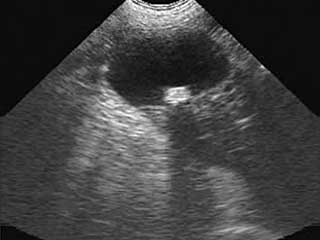

- УЗИ мочевого пузыря. Исследование выявляет опухоли размером свыше 0,5 см. Наиболее легко обнаруживаются новообразования на боковых стенках пузыря.